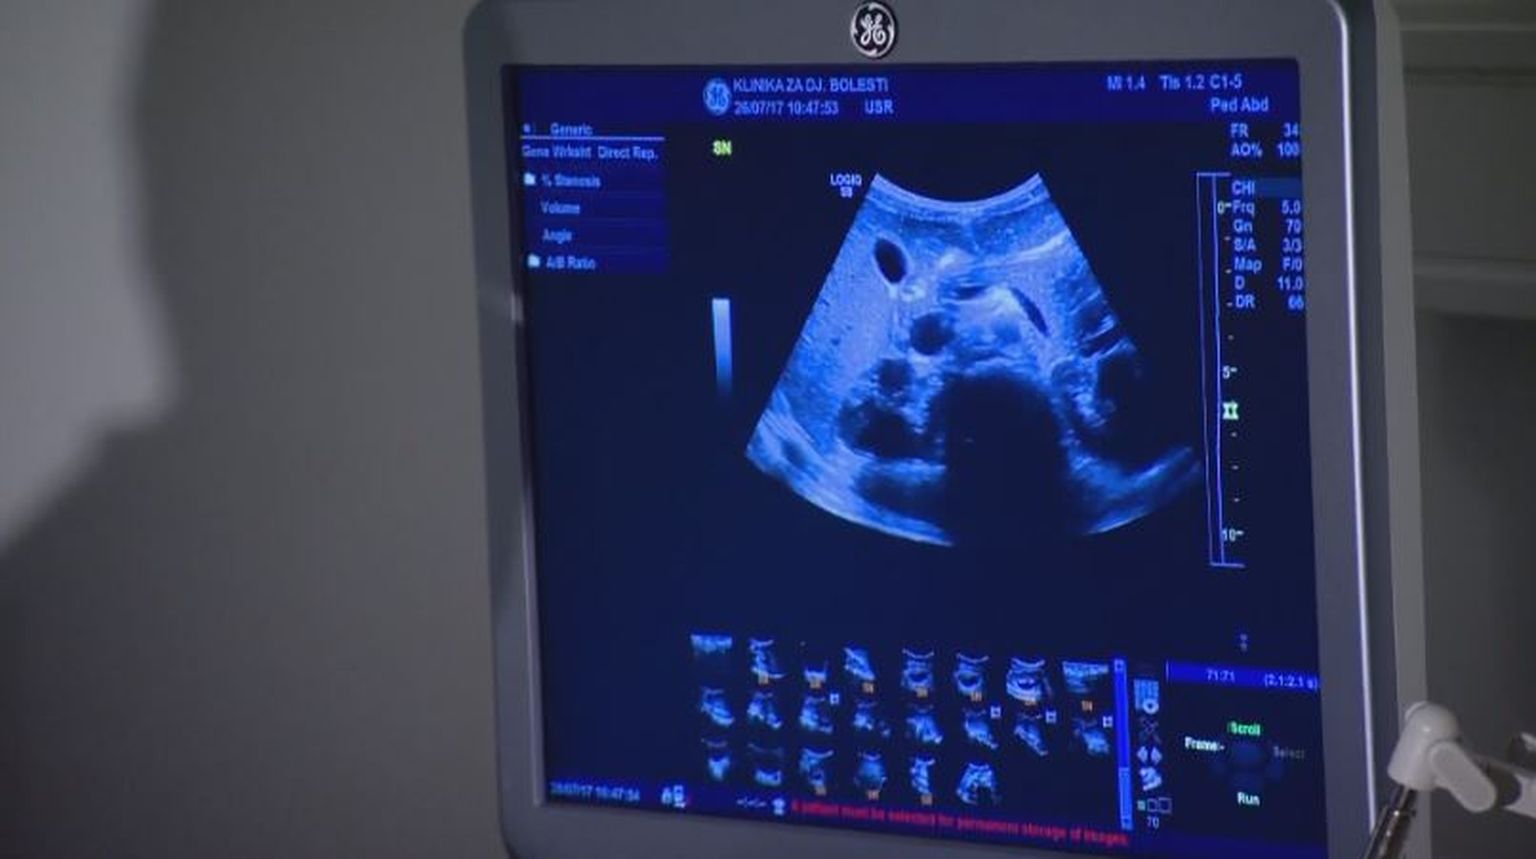

• Snimka ultrazvuka (Foto: Dnevnik.hr) Foto: DNEVNIK.hr